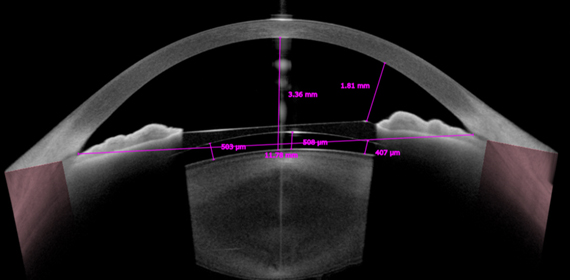

안내렌즈삽입술 전/후 평가

정확한 전안부 측정 (전방각 거리, 전방 깊이, 홍채 모양)이 가능하며, 조절력에 의한 구조적 변화를 예측하여 개인에 가장 적합한 렌즈 선택이 가능합니다. 또한 수술 후에는 삽입된 렌즈의 위치를 정확히 측정하여 렌즈로부터 각막 및 수정체까지의 거리를 측정할 수 있어 수술 후 정확하게 수술결과를 평가할 수 있습니다.

ICL 수술 후 vaulting